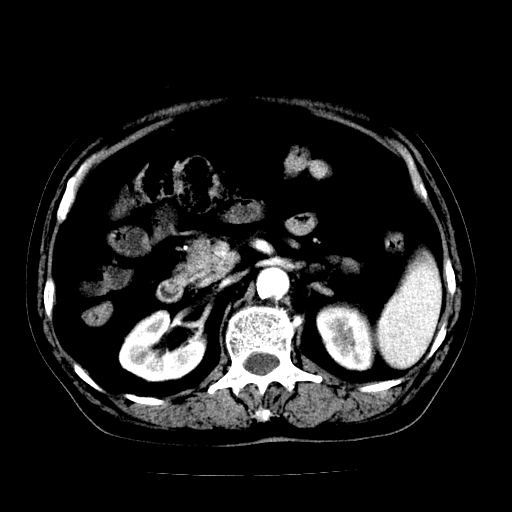

男,71岁,皮肤黄染四天。

肝内外胆管及胆总管上段扩张,考虑为梗阻所致,建议mrcp检查。

胰腺上端胆总管内见软组织影,强化不明显,结合临床,还是考虑低位梗阻性黄疸,胆总管癌可能性大